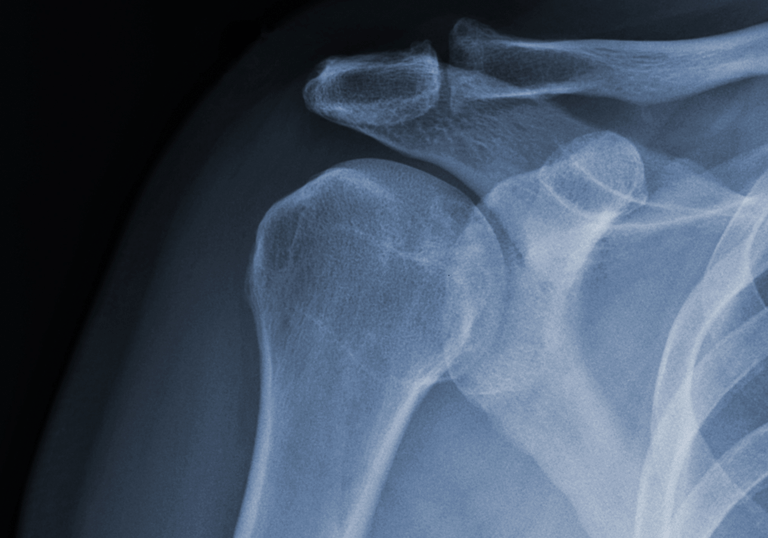

Evaluamos y tratamos lesiones que afectan los huesos, músculos, ligamentos y tendones. Desde fracturas y luxaciones hasta lesiones de tejidos blandos, ofrecemos un manejo médico y quirúrgico adecuado para una recuperación óptima.

Cirugías Ortopédicas Avanzadas.

Realizamos procedimientos quirúrgicos especializados, como:

Artroscopia: Técnica mínimamente invasiva utilizada para diagnosticar y tratar lesiones articulares, como desgarros de meniscos, lesiones de ligamentos y problemas en el cartílago.

Reemplazos articulares (prótesis de cadera, rodilla y hombro).